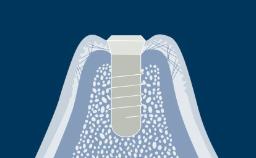

Additionally, the drugs that patients take and the conditions for which these drugs are required can influence the progress and outcome of implant treatment.

- describe medications or conditions that might influence the healing process following implant surgery

- describe medications that can impact on implant treatment in other ways